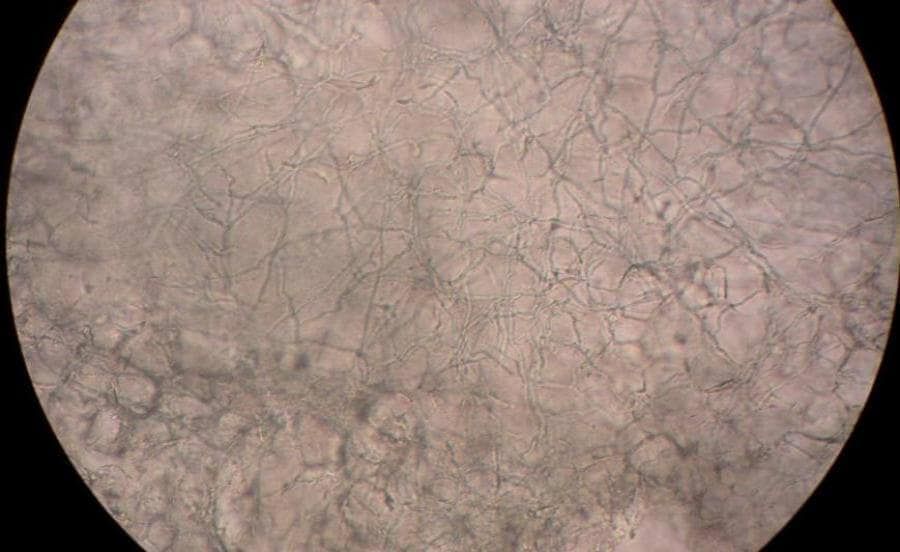

Een andere vorm van eczeem aan de (handen en) voeten is dyshidrotisch eczeem. Bij deze vorm van eczeem ontstaan er allemaal kleine, met vocht gevulde, blaasjes aan de handen en voeten. Wat hierin typerend is, is dat deze blaasjes vaak grijzig van kleur zijn.

Een bekende vorm van eczeem aan de (handen en) voeten is dyshidrotisch eczeem. Bij deze vorm van eczeem ontstaan er allemaal kleine, met vocht gevulde blaasjes op de voeten. Wat hierin opvalt is dat de blaasjes vaak een wat grijze kleur hebben. Wel moet ik zeggen dat dishydrotisch vaker voorkomt op de handen dan de voeten.